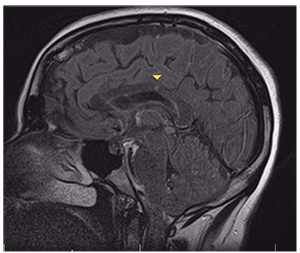

She was admitted to the hospital. Brain MRI showed a focal hyperintense signal abnormality on the fluid-attenuated inversion recovery (FLAIR) sequence in the corpus callosum, multiple punctate areas of diffusion restriction in the subcortical white mater, and an old right thalamic infarct (Figure 3, page 12).

| Figure 3. Fluid-attenuated inversion recovery MRI shows a focal hyperintense foci in the corpus callosum (arrowhead). |

Brain lesions tend to include small white matter lesions with a special predilection for the corpus callosum. MRI often shows focal hyperintensity on T2 or FLAIR lesions when they are acute and hypointense holes on T1 imaging when they are chronic.8 It is important to distinguish these lesions from those of multiple sclerosis because they can both involve the deep white matter, but demyelination is not typical of Susac syndrome.9